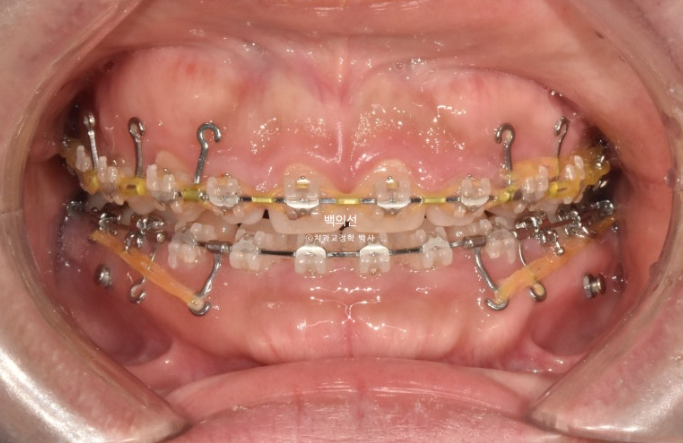

25.02